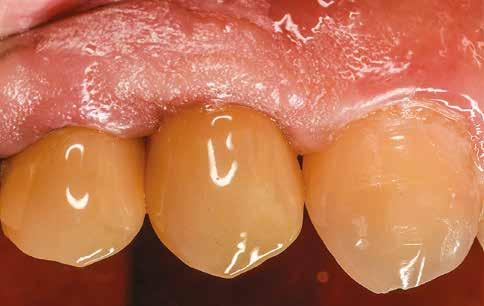

Az eljárást helyi érzéstelenítés mellett végeztük (4%-os articaine-hidroklorid 1:100 000 adrenalinnal). Papillakímélő, U alakú palatális bemetszést végeztünk, teljes vastagságú nyálkahártyalebeny preparálás történt, a lebenyt bukkálisan feltekertük (5. ábra). A lebeny bukkálisan feltekert részén de-epitelizációt végeztük el, amellyel kompenzálni tudtuk a bukkális lágyszöveti defektust. Szakaszos előfúrást végeztünk, és a bredent copaSKY 4x10 implantátumot 30 Ncm behajtási nyomatékkal helyeztük be (6. ábra). Az implantátumot 1 mm-re szubkresztálisan helyeztük be, hogy később szélesebb emergenciaprofilt tudjunk kialakítani (7. ábra). Az egyedi ínyformázó úgy készült, hogy kompozitot vittünk fel a titánbázisra, és így formáztuk a lágyszöveteket a transzgingivális gyógyulási fázis során (8. ábra). Az egyéni ínyformázó tulipán formájú, hogy kialakítsa a kívánt emergenciaprofilt. A lágyszövetet feszülésmentesen zártuk #6/0 nem felszívódó, monofil fonallal (Optilene, B. Braun Deutschland; 9. a–b. ábra). Posztoperatív röntgenfelvétel készült, ami alapján az implantátum a szomszédos fogakkal párhuzamos elhelyezést mutatott (10. ábra). Posztoperatív utasításokat adtunk a páciensnek a műtéti terület körüli szájhigiénia fenntartása érdekében. A beavatkozást követő egy héttel a varratokat eltávolítottuk, és a kezelt terület kielégítő gyógyulást mutatott (11. ábra). A 4 hónap utáni késleltetett terhelést a páciens kívánsága szerint terveztük.

uni.fit titánalapra (bredent medical). Az implantátum körül a bukkális lágyszövet megfelelő vastagságot és kedvező ínykontúrt mutatott (12. a–b. ábra). Az egyedi ínyformázó eltávolítása után egészséges implantátum körüli lágyrészgallér

volt megfigyelhető (13–14. ábra), ezen kívül közvetlenül a műtét előtt intraorális vizsgálatot végeztünk a lágyszöveti profil megállapítása érdekében. Ezt követte a scanbody behelyezése, így digitális lenyomat készült az implantátum pozíciójáról (15. ábra). Ugyanezzel a technikával rögzítettük az antagonista fogívet és a harapást is. Az így kapott STL-fájlokat digitálisan továbbítottuk a fogtechnikai laboratóriumba. A titánalapra PMMA ideiglenes koronát készítettünk a proximális és marginális illeszkedés ellenőrzése érdekében, valamint a megfelelő harapás elérése céljából (16–17. ábra) Miután az összes igazítás elkészült, ismételt vizsgálatot végeztünk. A végleges hibrid csavarrögzítésű, teljes kontúrú cirkóniumkoronát titánalapon erősen polírozott szubgingivális résszel készítettük el, és 25 Ncm nyomatékra húztuk (18. ábra). Kiváló árnyalategyezést és klinikai eredményt